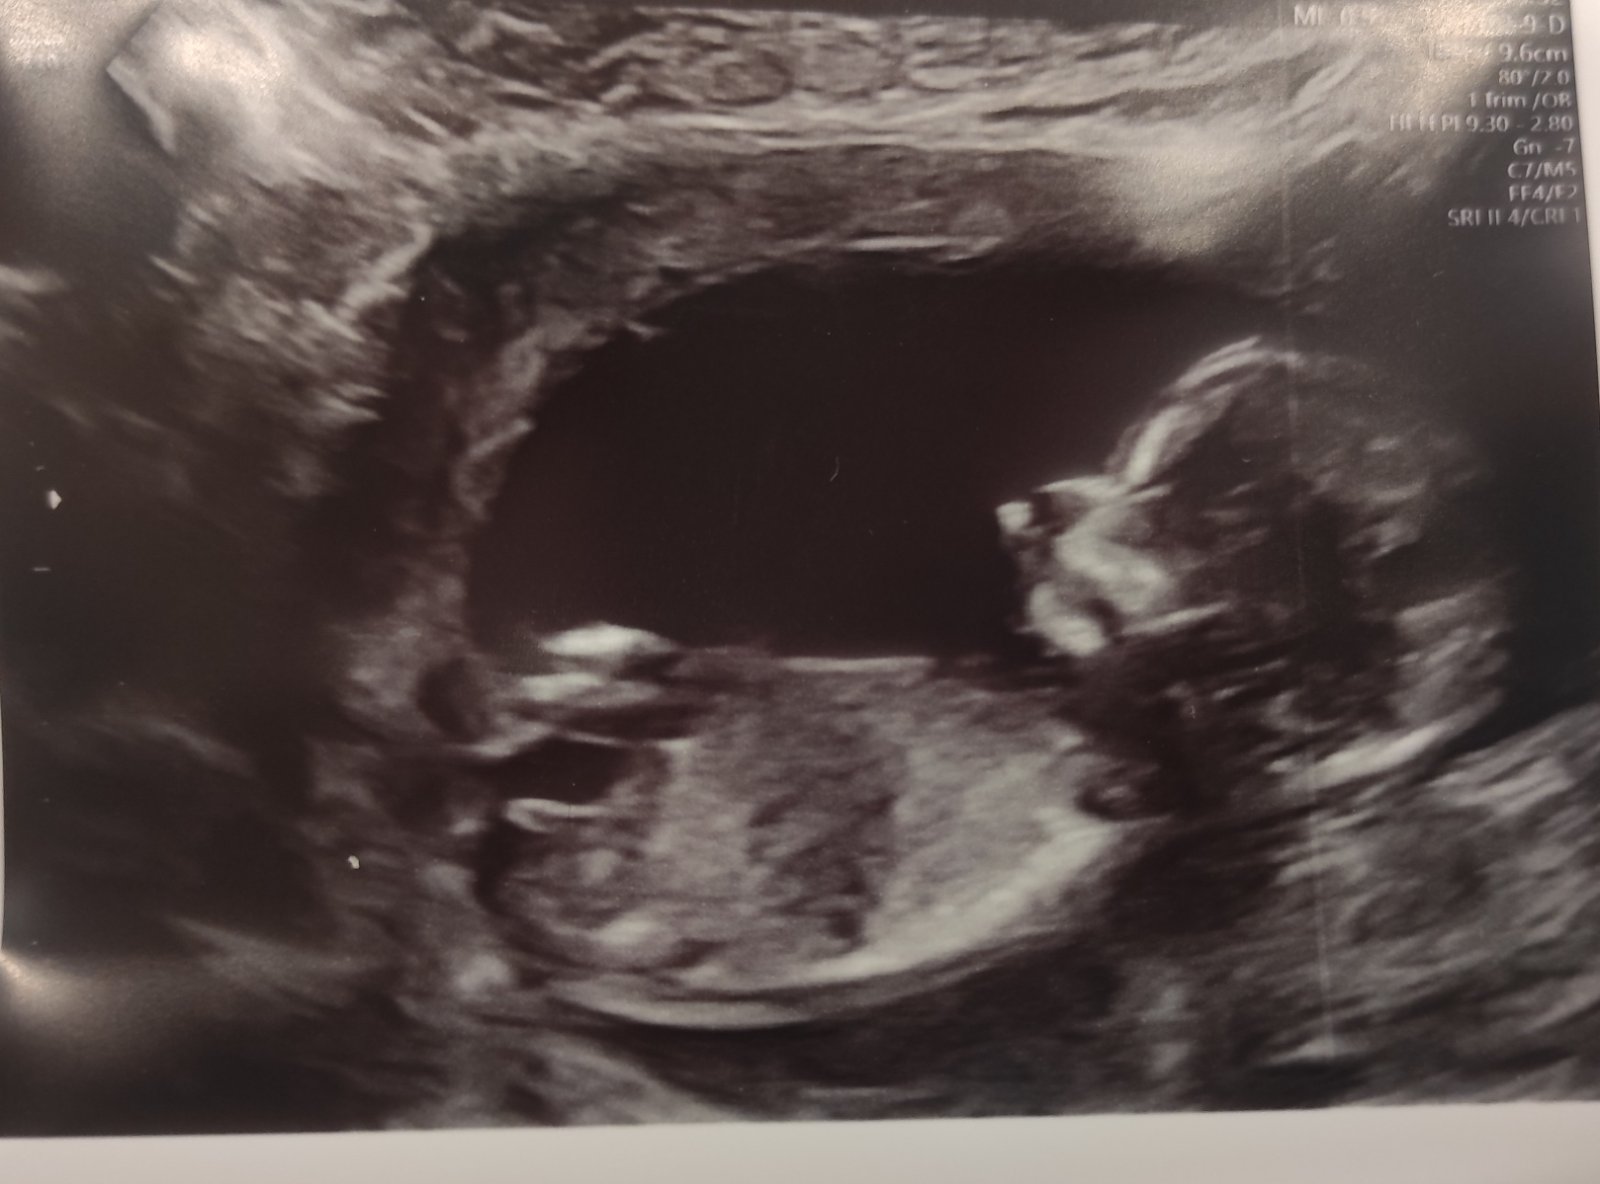

Ahoj holky, poznáte podle pohlavního hrbolku (pokud tam vůbec je 😂) pohlaví? Dnes na screeningu mi tvrdili, že je to chlapeček, ale já ať se koukám, jak se koukám, vychází mi to na holčičku 😂🤷🏻♀️

Komentáře typu, že mám počkat atd. netřeba 🙏 je mi úplně jedno zda, to bude to či ono, jen mě zajímá názor ostatních, protože já to vidím prostě opačně 😂

@chybadel joo? 😁 přijde ti ten sklon větší než 30°? 😁 mně to právě přijde souběžné 😁

Já bych podle této fotky tipla spíš holku… Všichni moji 4 kluci ten hrbolek měli výrazně nahoru oproti tomuto 🤷🏻♀️ To mě fakt zajímá, co poví příště 😁

Taky bych spíš řekla holka, ale přijde mně, že se trošku výš stáčí.., ale jestli se mně to nezdá, když vím, že to má byt chlapeček. Co máš doma?

@jaja01k jsem na to zvědavá, co se dozvím třeba ve 20.tt 😁 ale dle UTZ bych řekla téměř ukázková holčička 🤷🏻♀️ na druhou stranu, kdyby to byl opravdu chlapeček, tak aspoň nemusím nic řešit - všechno mám už doma po starším 😂😂